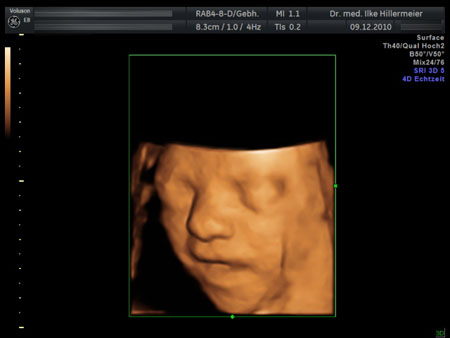

Ultraschalluntersuchungen in der Schwangerschaft

27. Schwangerschaftswoche

27. Woche